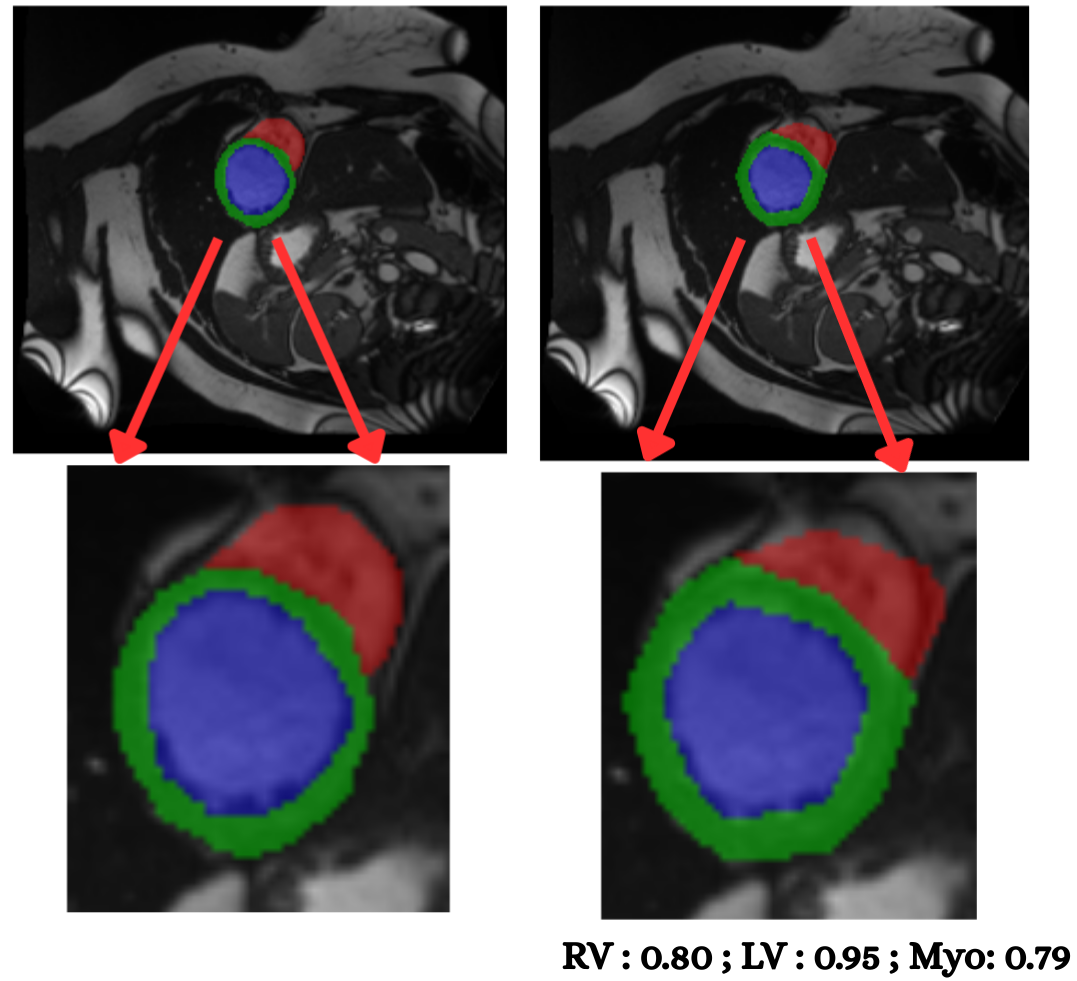

To evaluate cross–modality transfer, we perform few–shot fine tuning on the CAMUS echocardiography dataset, using only {5, 10, 20, 50} labeled samples from a single clinical site. Unlike MRI, ultrasound poses a significantly harder segmentation challenge due to acoustic artifacts, speckle noise, anisotropic contrast, and view–dependent anatomical deformation. Despite this domain gap, Figure 10 shows that PULSE progressively adapts to ultrasound geometry with increasing supervision. With only 5 labeled cases, the model produces coarse chamber boundaries and myocardium leakage, yet still recovers the global cardiac shape (mDice 0.612, mIoU 0.468). At 10 samples, segmentation accuracy improves substantially, with clear endocardial delineation and reduced basal drift (mDice 0.696, mIoU 0.556). Fine tuning on 20 cases leads to stable myocardium recovery (mDice 0.746), suggesting that the model internalizes modality–invariant structure once minimal supervision is available. At 50 cases, performance reaches near–MRI quality (mDice 0.815, mIoU 0.705), approaching full–data performance and producing visually crisp LV and RV walls even under ultrasound noise. These results demonstrate that PULSE can retain cardiac anatomical priors learned from MRI and rapidly transfer them to ultrasound with very limited supervisiona desirable property for deployment in low resource hospitals where complete annotation is rarely available. The smooth improvement across shots also reinforces the quantitative trend of Table 12, validating few–shot echocardiographic adaptation as a viable clinical pathway for real-world integration into emergency, bedside, and limited–annotation scenarios.